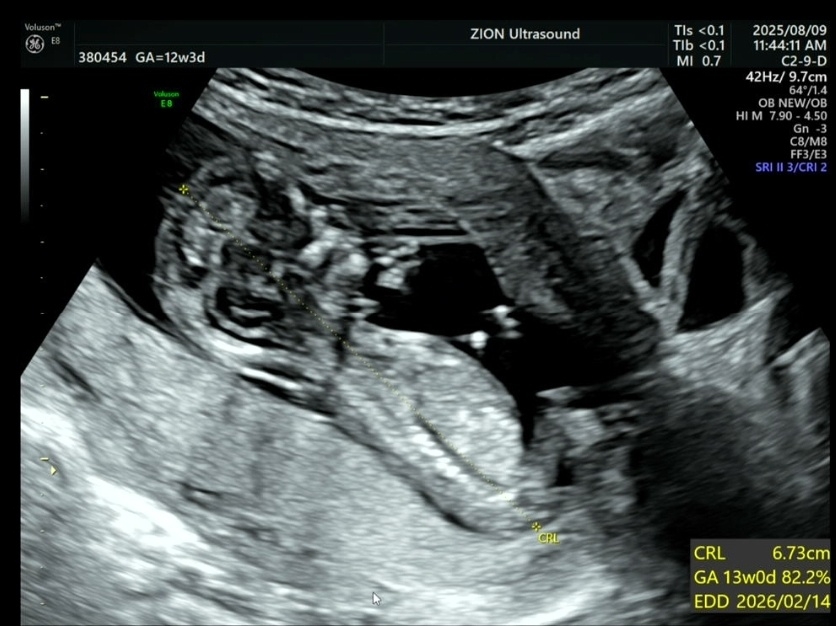

12주차 3일 각도법 고수님들 봐주세요 🥹🩷

각도법 고수님늘 딸일까요 아들일까요?